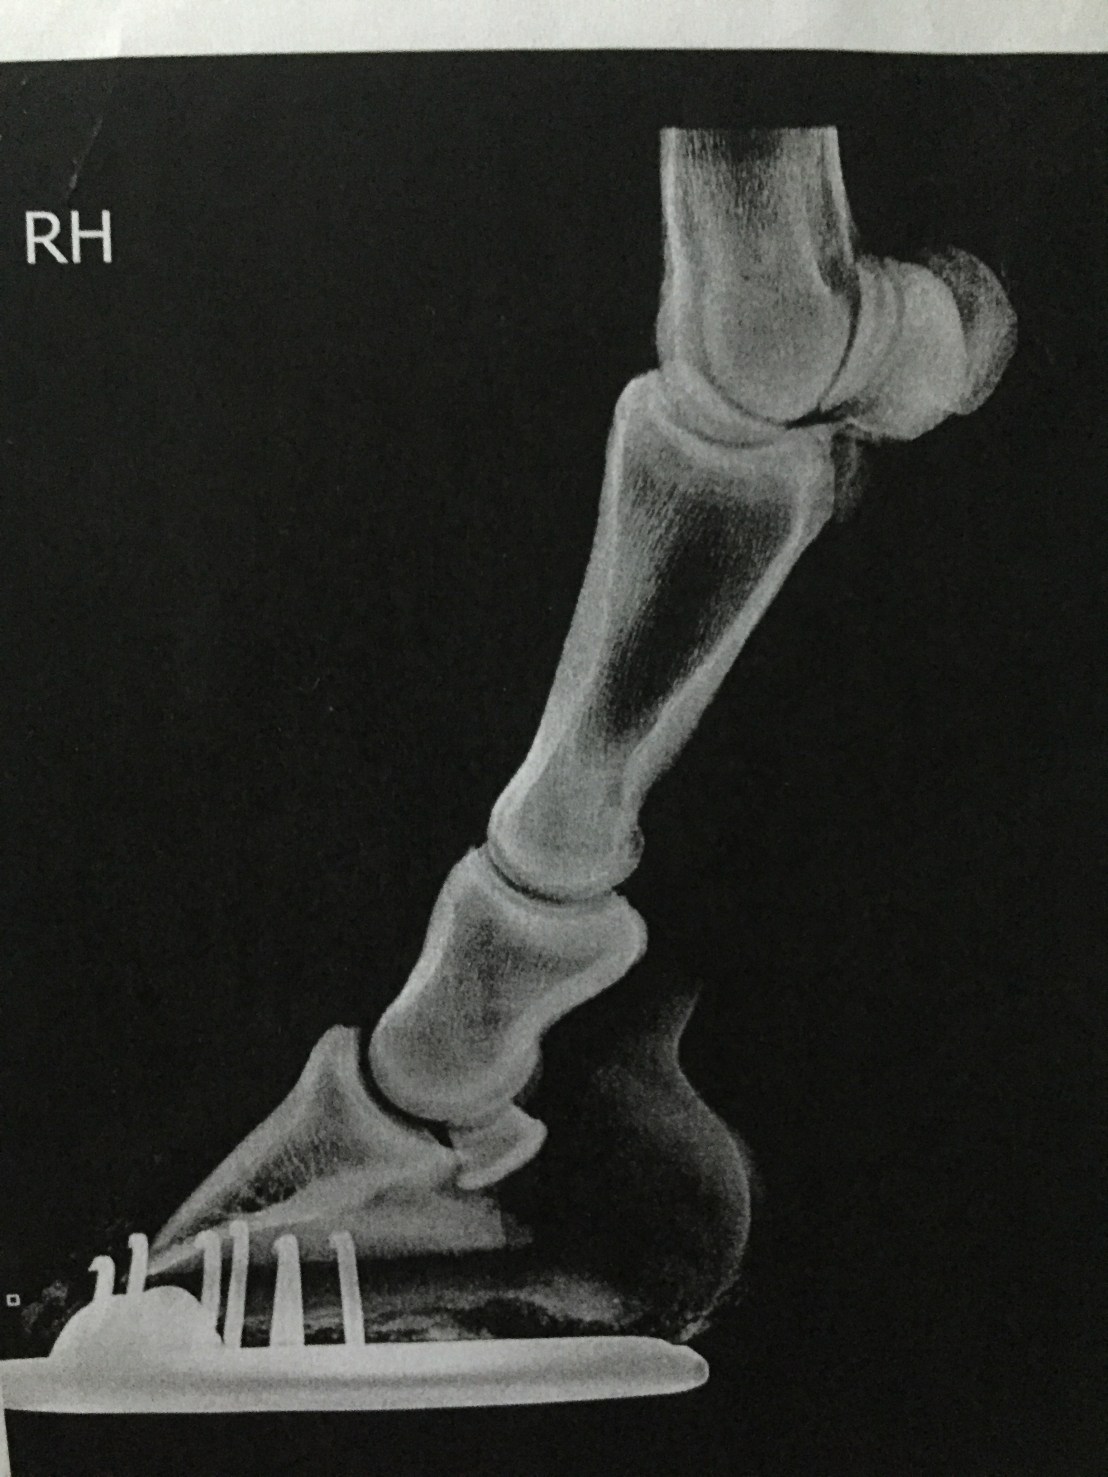

Frank has been on the sick now for two months. Initially he presented with a really sore back back, shoulder and hamstring. I have no idea how he has done this. Two days before the wheel fell off, we came second on a 1m showjumping class -just two seconds behind the winner. This effort was followed by a day off (field turnout) and a steady hack on the second day. On the third day towards the end of a flatwork session practising a couple of Novice tests someone notices his saddle is lifting off his back. Shortly after this Frank stops and cow kicks his belly as if trying to remove a pesky fly and then refuses to move forward- it was like trying to push a wonky shopping trolley. Since he won’t go forward and something is clearly bothering him I dismount feeling sure that there is something wrong with the dressage saddle. I turn him out and Frank has a good roll in the mud and a gallop round the field bucking with glee at being set free. Hmmmmm? he doesn’t look that much in pain does he? Next day he has a day off and on Saturday we box up to a yard with a solarium. He’s still in discomfort Saturday afternoon so we have no choice but to withdraw from Sundays dressage competition and I feel like my world is capsizing. Ten days after Frank’s initial symptoms appeared he has a two hour appointment with Imogen Gifford, physiotherapist. Deep tissue massage, ultrasound and laser therapy to back muscles which appear hard and unyielding. Tuesday appointment with Bethan Lloyd who found similar soreness and realigns a rib. By Friday 25 January he’s no better. The following Monday I make an appointment with Cotts Wednesday 30. As he is trotted up , slight unevenness behind is noted. Lunging in the round pens makes this more obvious. Investigation of hind limb lameness blocked to the left stifle and Frank was prescribed previcox 57mg/day for 30 days then half a tablet for 20 days. Xrays of feet and hocks show no arthritic or bony changes. Both hind xrays show broken back between pedal bone and short pastern – this is being remedied by my farrier who was now able to see exactly what was going on.

This could possibly be affecting Franks stifles. Conservative remedial farriery has reduced this angle by about 3 degrees.